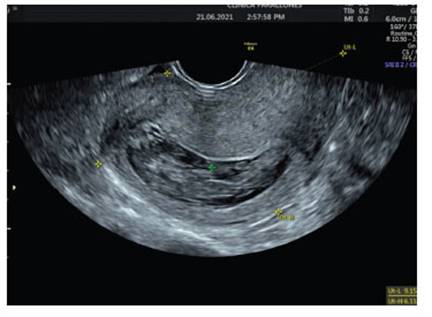

After 8 days, the patient consulted again for pelvic pain and persistent heavy bleeding. A new ultrasound showed a 17 mm thickened endometrium (Figure 3). The pathology results of the previous curettage were reviewed and showed decidual fragments and placental debris, respectively. Medical management with misoprostol was decided and the patient was discharged.